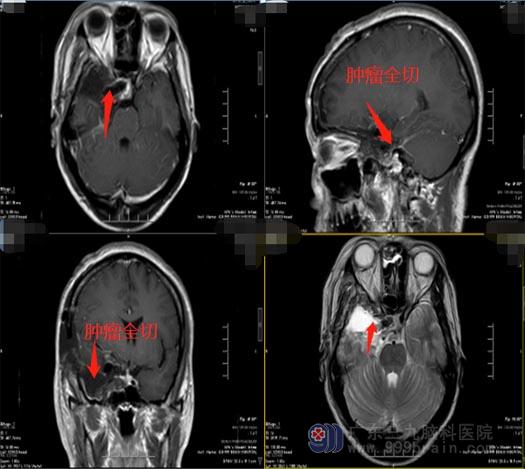

医院副院长、神经外五科主任鲁明带领治疗团队为柯女士先进行了脑血管造影+Allen试验+Bot试验,预先了解肿瘤及颅内血供情况,排除了手术禁忌症,为患者实施了“右侧鞍旁-蝶骨嵴脑膜瘤切除术+右侧颞浅动脉-右侧大脑中动脉血管搭桥术”,术中发现颈内动脉被肿瘤严重侵犯,对颈内动脉进行了破口夹闭。手术顺利。柯女士术后恢复得很好,四肢活动正常,很快就办理了出院,一家人都非常满意手术效果。术后病理结果提示:过渡型脑膜瘤(WHO1级)。复查头颅MR提示原病灶已切除。